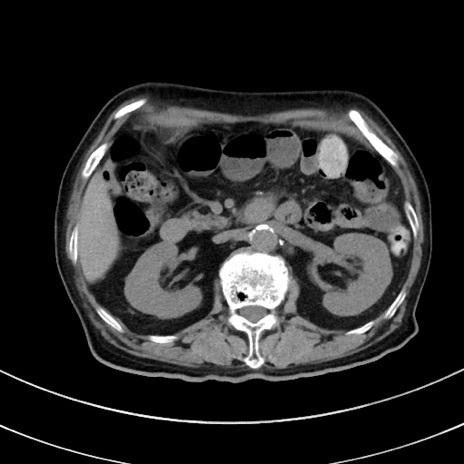

冠状断像

【症例】70歳代 女性

【主訴】心窩部痛

【現病歴】延髄病変の精査・加療にて神経内科入院中。本日より心窩部痛あり。

【身体所見】右下腹部を中心に圧痛と反跳痛あり。

【データ】WBC 10900、CRP 0.02